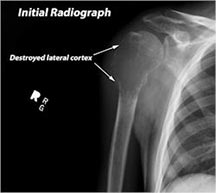

X-ray:

- Permeative lesion with indistinct border that is poorly marginated

- Osteolytic and expansile on X-ray with very little osteoid production

- May have Codman’s triangle and malignant appearing periosteal reaction in most cases

- Cortical destruction and soft tissue extension are common